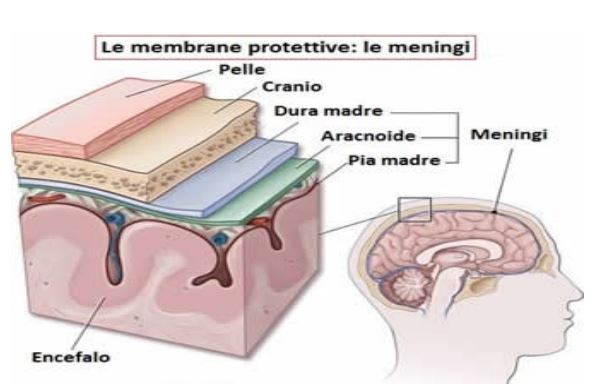

- Ematomi, dovuti a emorragie cerebrale per rottura di vasi sanguigno di grosso calabro e che possono localizzarsi in diverse sedi, all’esterno del tessuto cerebrale o all’interno. A secondo la sede si dividono in

1. Ematoma epidurale o extra durale

2. Ematoma sub durale

3. Emorragia sub aracnoidea

Qui di seguito sono riportate schematicamente le sedi, dove maggiormente si localizzano gli ematomi e alcune immagine di TAC del cranio che mostrano alcune lesioni cerebrali.

Ematoma extra durale, ematoma sub-durale emorragia intracerebrale